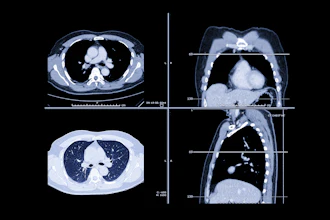

Cases of the Week

Check out our Cases of the Week!